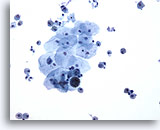

Figure 1

Bronchoalveolar lavage

Low magnification showing an admixture of epithelial cells and macrophages. 20x

Bronchoalveolar lavage

Low magnification showing an admixture of epithelial cells and macrophages. 20x

Figure 1

Bronchoalveolar lavage

Low magnification showing an admixture of epithelial cells and macrophages.

20x

Bronchoalveolar lavage

Low magnification showing an admixture of epithelial cells and macrophages.

20x